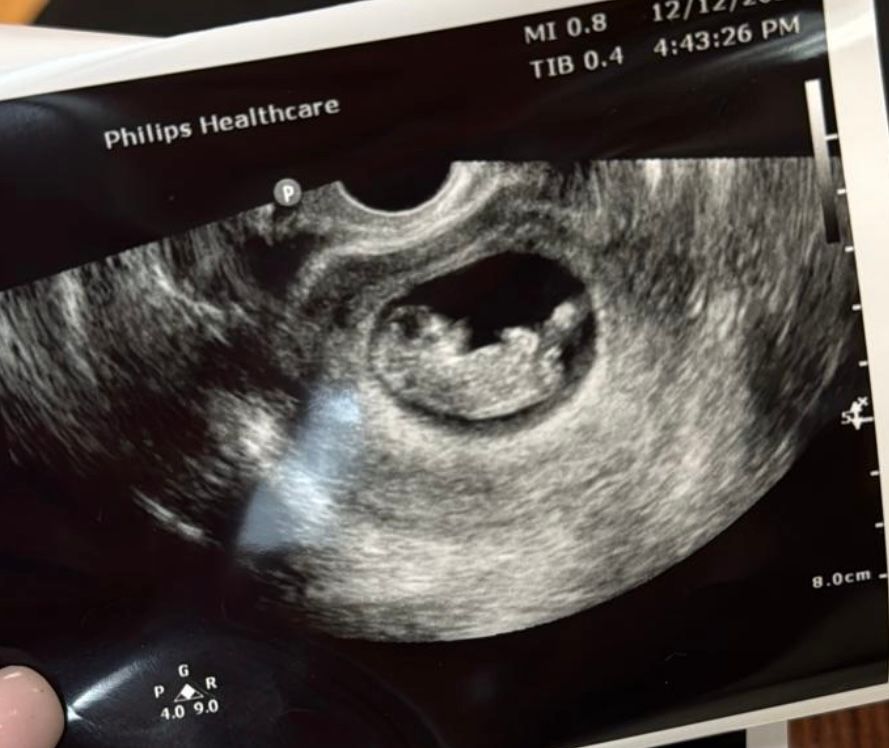

Девочки успокойте. У кого так было? Пульс ребенка в 12 недель.

12 недель беременности. Сегодня была на приеме гинеколога. Датчиком не могли найти пульс, давила везде слушала, еле как прослушивалось. Тут же привезла аппарат узи. Сердце бьется, малыш двигается. Но пульс по узи не удалось включить, потому что это не тот аппарат который нужен. Она нашла место положение малыша и снова начала искать сердцебиение